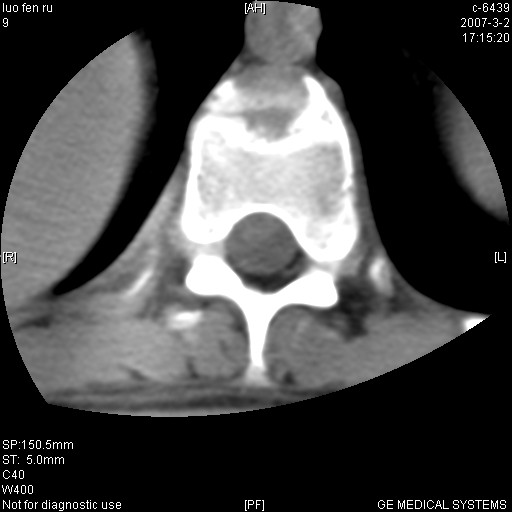

标题: CT6952:T11椎体病变请讨论

女,19岁.背部疼痛一月余.自诉幼时有个外伤史.

腰椎平片示,t11椎体呈楔形改变,椎间隙未见异常.

当是应是椎体(前半部较厉害)压缩性骨折,这就印证了这就是陈旧性骨折。

t11椎体前缘不规则形骨质破坏,周围有硬化边,软组织肿块不明显,首先考虑:骨嗜酸性肉芽肿 。期待随访结果。